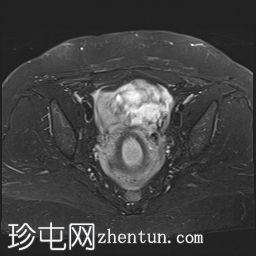

矢状位

T2加权像

可见子宫外腹腔内妊娠囊,内含胎儿组织。

该妊娠囊向后推移子宫,并与剖宫产瘢痕凹陷处紧密相连。

该妊娠囊与相关肠袢无法分离。可见其与性腺血管密不可分,且性腺血管明显突出。

胎盘位于妊娠囊后方,紧贴子宫前壁。

沿妊娠囊下缘可见一处异质性局灶性积液,最大轴向尺寸约为 8.4 × 5.5 cm,T1 加权像呈异质性高信号,T2 加权像呈异质性中等信号,T1 脂肪抑制序列未见信号下降,提示为血液成分。该积液压迫膀胱。

可见周围脂肪间隙呈条索状改变。

左侧卵巢无法辨认。

右侧卵巢未见实性或囊性肿块。

子宫体积增大,后倾,子宫内膜厚度约 1 cm,子宫下段前壁可见局灶性变薄(既往子宫瘢痕)。子宫连接区完整,未见肌层肿块。可见子宫内膜腔边缘有血性分泌物。